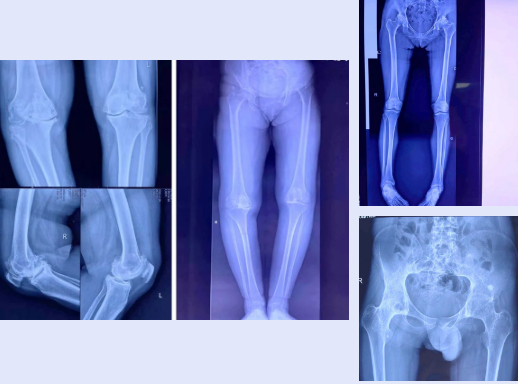

▲术前影像资料

尤其是一位年仅20岁强直性脊柱炎继发重度双髋骨关节炎伴关节僵直畸形患者,因他长期无法就坐,只能常年站立,严重影响基本生活,荒废学业。辍学后曾在全国各大医院就诊、治疗,症状有所缓解,但未根除。近日因病情复发,遂来我院骨三科就诊。入院后,骨三科主任杨小广和主治医师邵誉亮组织全科医师讨论,决定邀请华西专家远程会诊,会诊后将治疗方案通知家属和本人,患者同意我院和华西专家共同完成手术。术后仅仅1天,患者髋关节可以开始主动活动。